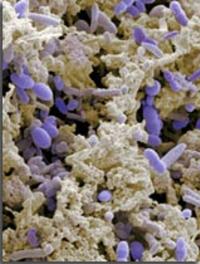

Près de 3 femmes sur 4 font l’expérience au cours de leur vie d’une mycose vaginale. La moitié d’entre elles présentent une récurrence [...]

En dépit de nouveaux traitements plus efficaces et plus sûrs, les candidoses invasives et les candidémies restent entachées d’une forte [...]

L’incidence croissante des candidoses invasives chez les malades gravement atteints a conduit au développement de nombreuses molécules [...]